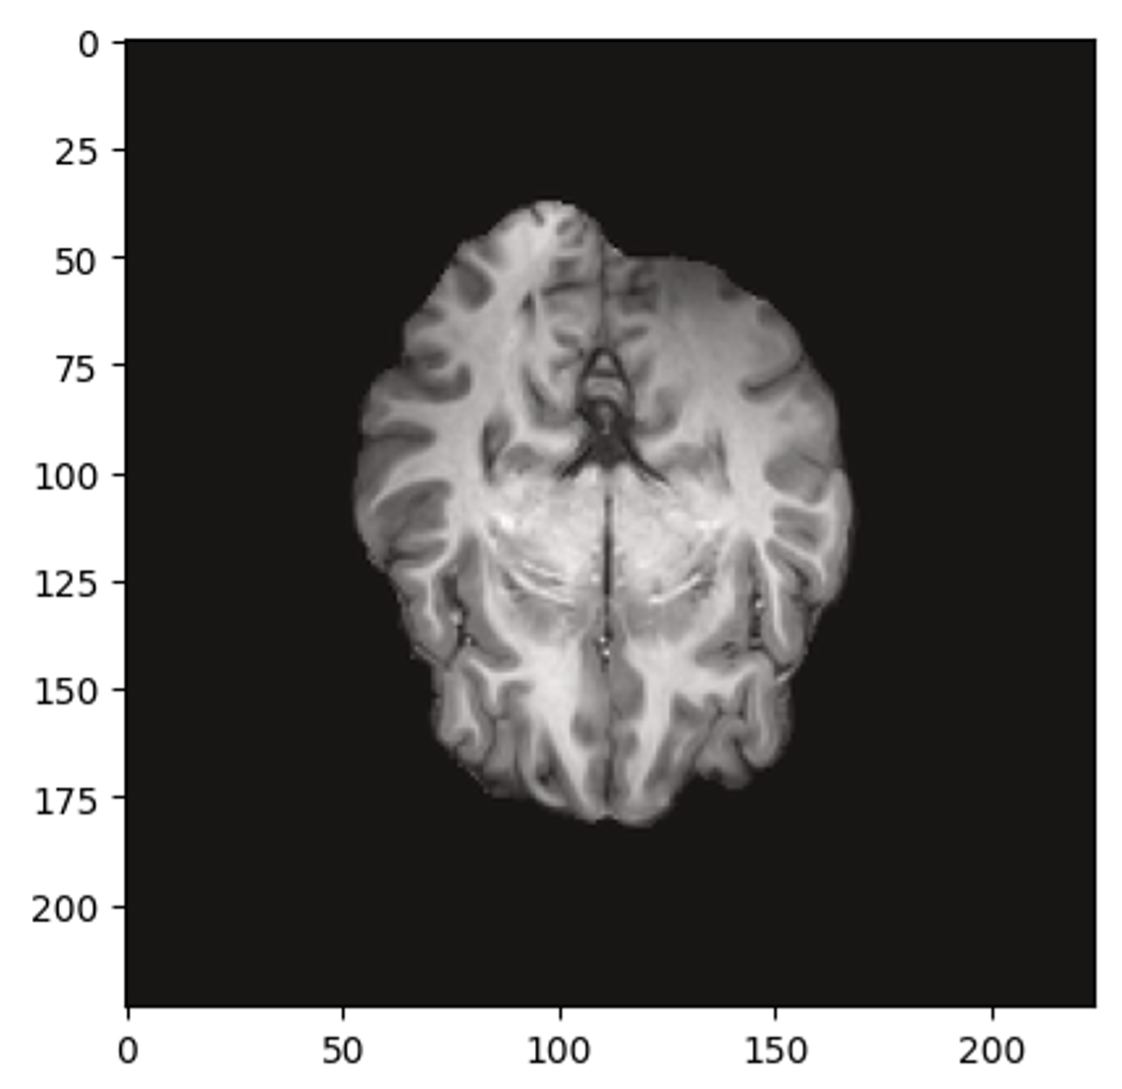

[Uncaptioned image]

Figure 1: TRS-MRI Sample: An example of a 2D resting-state MRI scan acquired from the UCLA Consortium and pre-processed with NumPy.